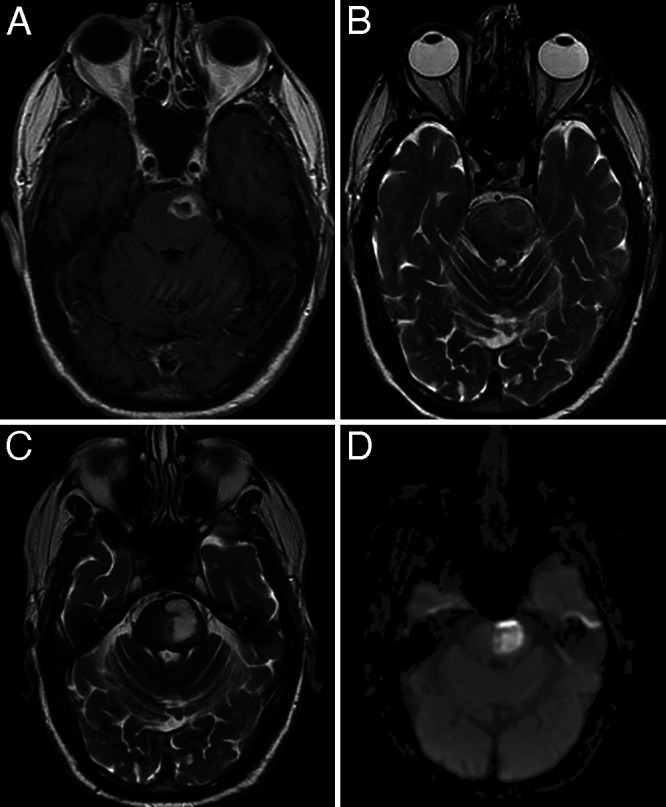

A 70-year-old male presented to the hospital with the chief complaint of dysarthria. His past medical history was significant for atrial fibrillation and type 2 diabetes mellitus. He had no history of malignancy, transplantation, or chronic infection that might confer immunosuppression. His neurological examination at presentation showed right hemiparesis and facial drop of central origin. Radiographic studies revealed a pontine lesion eccentric to the left with edema and restriction on diffusion-weighted imaging (DWI; Fig. 1A and B). These findings were interpreted as possible infection. The patient was started on empirical antibiotics despite noncontributory blood cultures, cerebrospinal fluid without evidence of meningitis, and negative encephalitis panels. An echocardiogram was performed and did not reveal evidence of a right-to-left shunt as a source for infectious emboli.

FIG. 1.

A: Axial T1-weighted MRI with gadolinium obtained at the initial presentation, showing a rim-enhancing lesion in the pons. B: Axial T2-weighted magnetic resonance image obtained at initial presentation, showing edema around the lesion. C: Axial T2-weighted magnetic resonance image taken 1 month after initial presentation, showing significant progression of the lesion. D: DWI showed restriction.

After several weeks, the mass enlarged and the patient’s hemiparesis worsened (Fig. 1C and D). Interestingly, the rim enhancement seen initially had diminished. On neurological examination, the lower half of his face on the right was almost immobile, and his speech was incomprehensible. Surgical evacuation was offered to the patient at presentation, but intervention was deemed too risky at that time by the patient, family, and his multidisciplinary care team. Given the clinical and radiographic progression with nonoperative treatment, however, surgery was reconsidered and deemed appropriate.